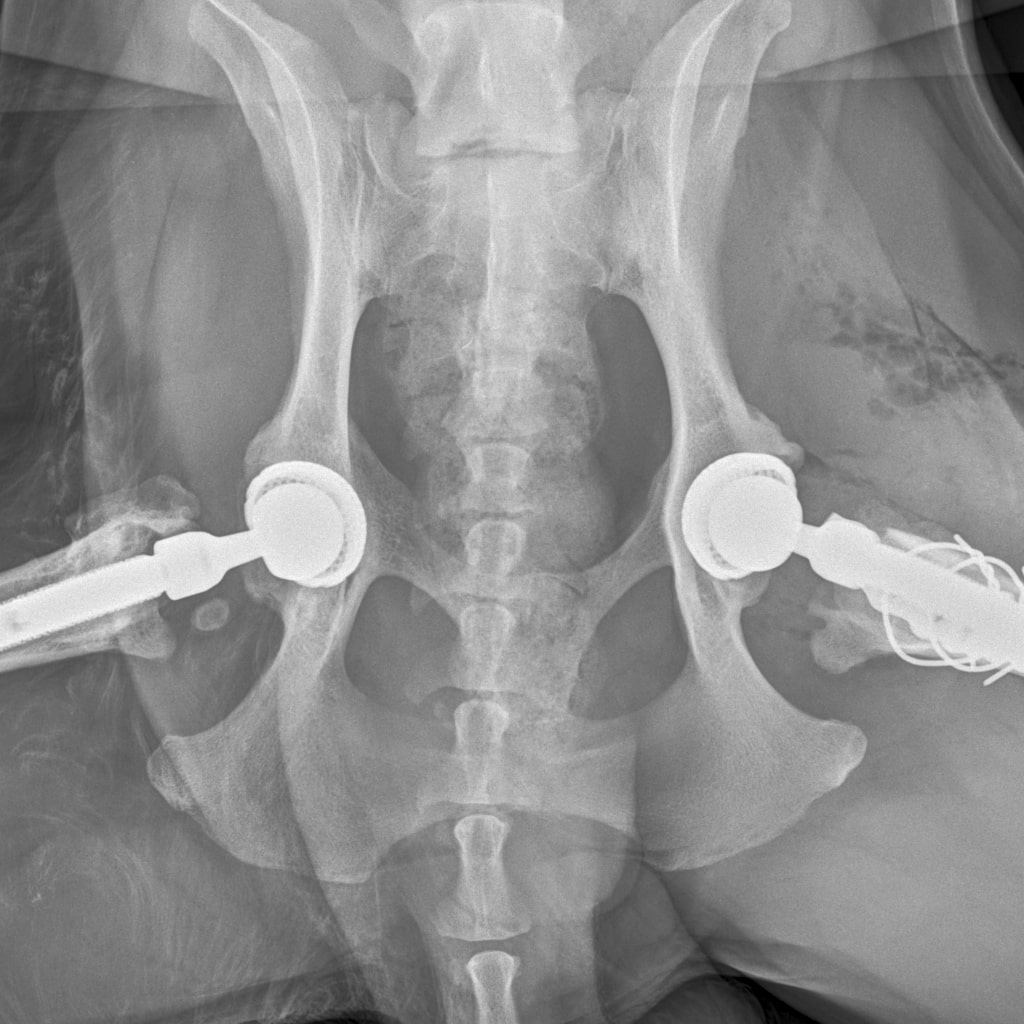

26 августа к 10 утра голодными, нас ждут на контрольный рентген в клинике на Вернадского.

Рентген будет под седацией

За время противовоспалительной терапии снизилось воспаление и в левом тазобедренном суставе, но увы, форма головки бедренной кости и состояние шейки бедра , лучше не стали:(((

Операция однозначно нужна.

Снимки столь качественные, что их можно в учебник

Железный дровосек